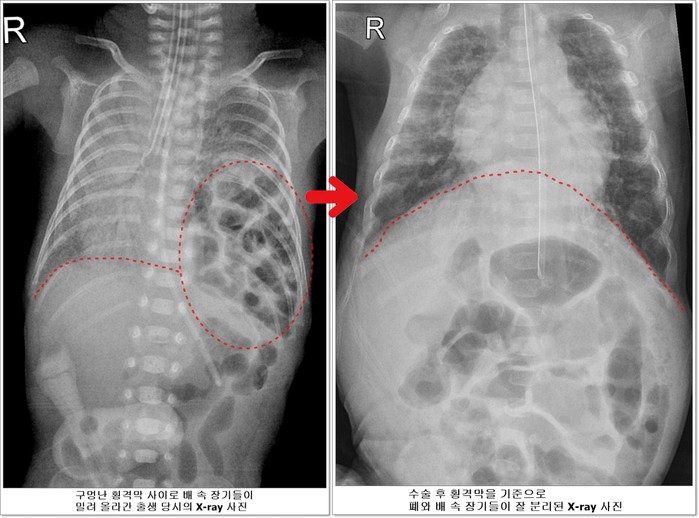

![]() |

| ▲전호삼 아기의 치료 전 후 X-ray사진 비교 |

선천성 횡격막 탈장증이란 가슴 안의 심장과 폐를 배 속의 소화기 장기들로부터 분리해주는 횡격막에 선천적으로 구멍이 나는 질환이다. 배 속의 장기가 횡격막의 구멍을 통해 밀려 올라와 가슴안의 심장과 폐를 압박해 폐가 제대로 펴지지 않아 호흡곤란이 오고 심장기능 또한 떨어지게 된다.

하지만 호삼이는 이 모든 과정을 다 이겨내고 태어난 지 40일이 되던 5월 20일에 체중 1530g이 되어 소아외과 남궁정만 교수가 구멍 난 횡격막을 막는 수술을 성공적으로 시행했다.